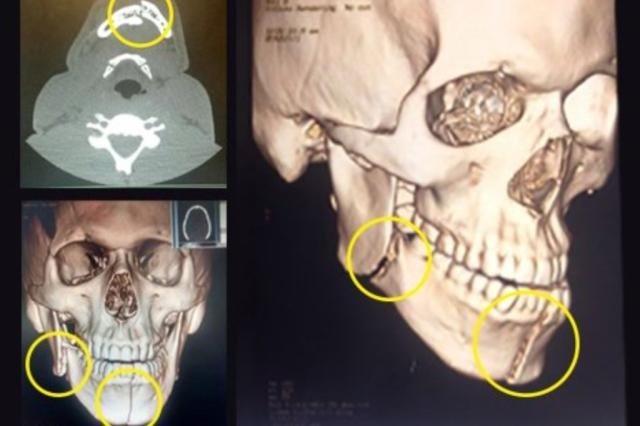

Clube, com autorização do jogador, publicou em seu site oficial as imagens

O Grêmio divulgou na noite desta segunda-feira os exames feitos no último domingo em Miller Bolaños. Nas imagens, divulgadas pelo clube com autorização do jogador, é possível ver os dois pontos onde aconteceram as fraturas.

Miller Bolaños teve a mandíbula (maxilar inferior) fraturada em dois lugares, após o cotovelaço de William, no começo do Gre-Nal 409. O equatoriano segue internado no Hospital Mãe de Deus, em Porto Alegre, onde permanecerá até a quarta-feira, quando realizará a cirurgia para a reconstrução do local – possivelmente com a colocação de uma placa.

O jogador sofreu duas fraturas com a pancada: uma na altura do queixo (chamado de linha média do rosto) e a outra ao lado direito da mandíbula. Após a operação, ele deverá permanecer por dois dias internado. Durante um mês, precisará se alimenta de refeições líquidas e pastosas, além de tomar anti-inflamatórios, a fim de reduzir o edema na boca.